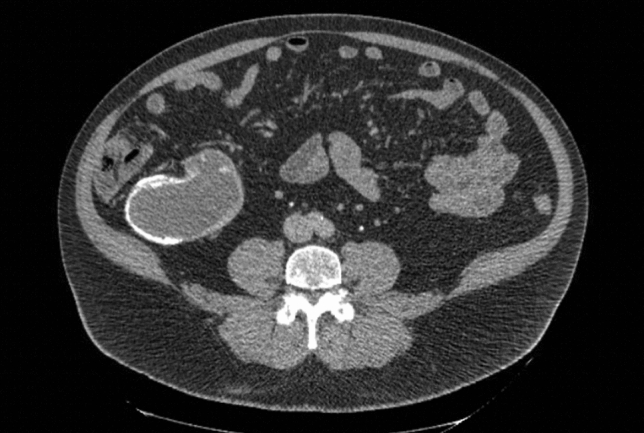

P041